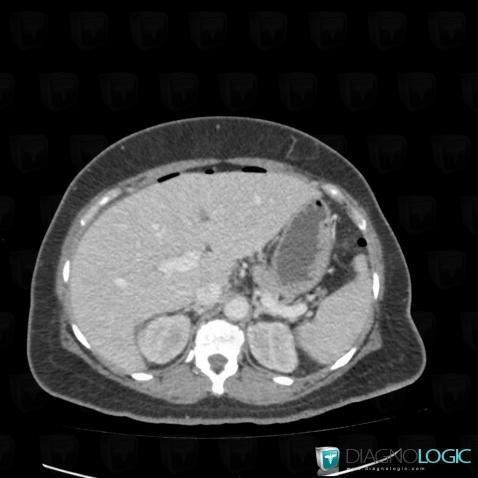

Pneumoperitoneum, Mesentery / Peritoneum, CT

Here is the specific information in the key image above:

- Diagnosis Pneumoperitoneum, Location(s) Mesentery / Peritoneum, with gamuts